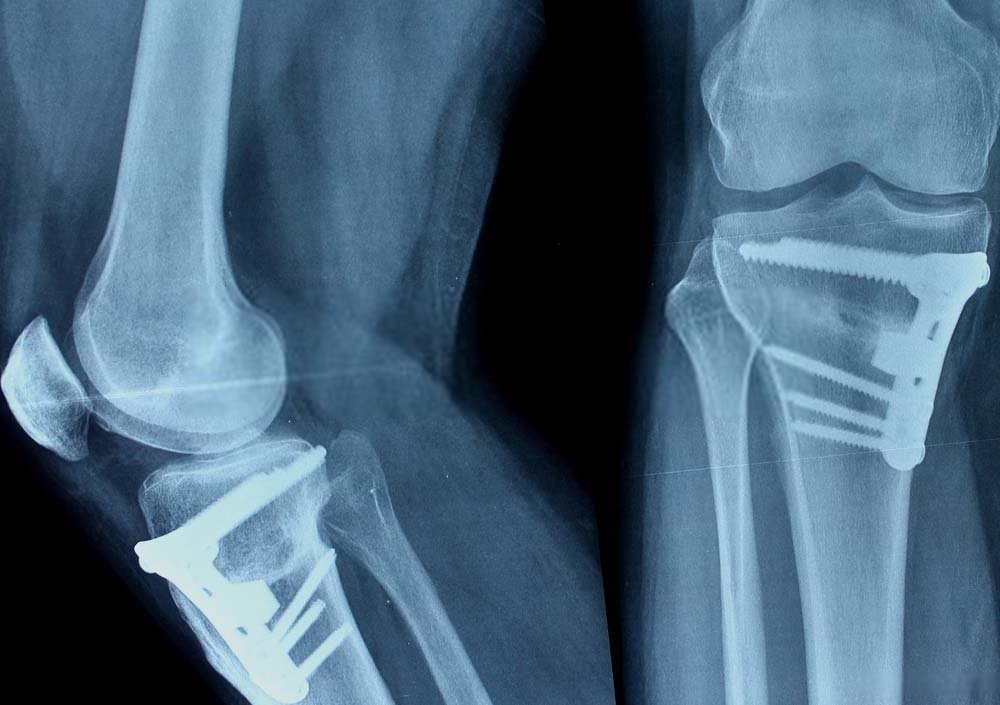

Knee Preservation Surgery

Knee preservation surgery in Kudasan, Gandhinag...